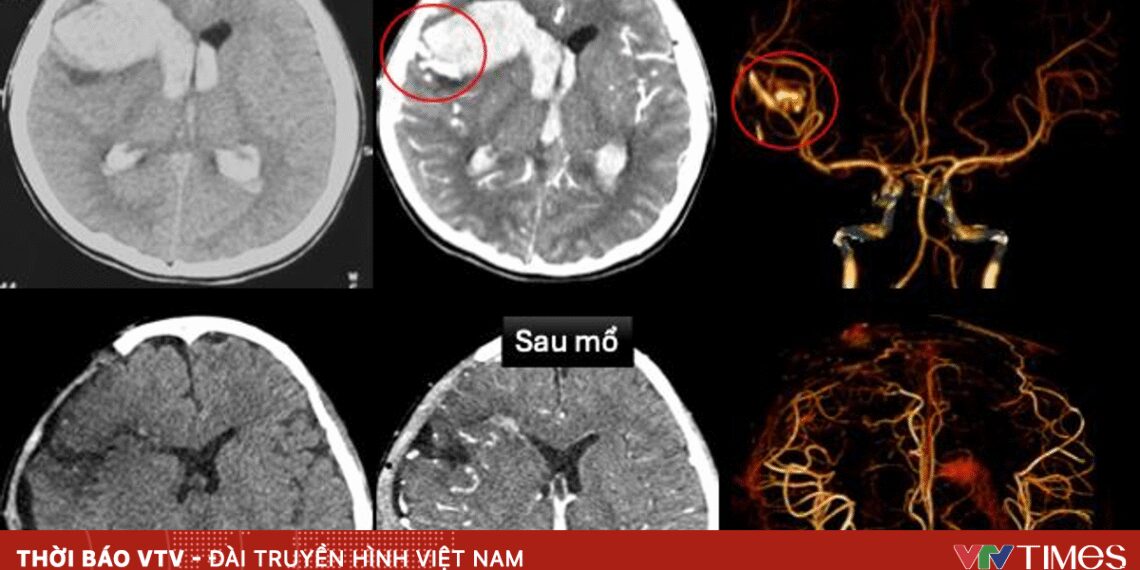

Tại Bệnh viện Nhi đồng 1, bệnh nhi được cấp cứu tích cực, siêu âm tim và chụp cắt lớp vi tính sọ não dựng hình mạch máu. Kết quả cho thấy dị dạng động tĩnh mạch trán phải vỡ, gây xuất huyết não lan vào não thất trên nền bệnh cơ tim xốp, một bệnh lý tim mạch bẩm sinh hiếm gặp.

Nhờ xử trí kịp thời, bệnh nhi dần tỉnh táo, vận động yếu nhẹ chân phải, tim mạch ổn định, đã rút máy tạo nhịp và ngưng thuốc vận mạch. Hình ảnh kiểm tra sau mổ cho thấy không còn dị dạng mạch máu, chức năng tim cải thiện rõ.